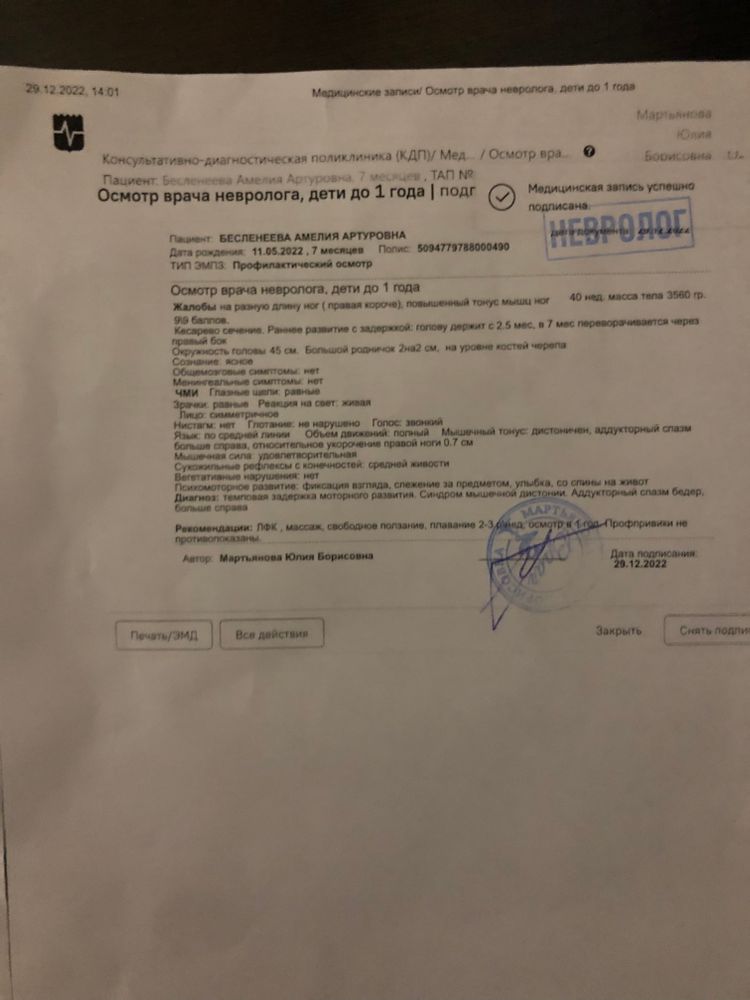

Малышке 7,5 месяцев, прошли второй курс массажа и на массаже мне сказали,что надо сходить к ортопеду,массажистке не понравилась правая ножка у малышки. Мы пошли к ортопеду,он осмотрел визуально нас,сказал,я ничего не вижу,но сходите на рентген. Пошли га рентген и там описали снимок,дали заключение вывих правого тазобедренного сустава ножки под вопросом. Дали нам направление на осмотр в клинике ортопедии и травматологии в Москве. Сегодня поехали туда,там нас осмотрел ортопед и невролог. Ортопед сказал,что визуально складочки на ножках не равномерно и правая ножка короче левой на 0,5 см, посмотрела наш снимок рентгена и сказала,что по снимку нет дисплазии. Сказала,что это тонус такой,мышечная недостаточность так сказать,ничего страдного,сказала делать массажи,плаванье,парафин и электрофорез.

Вот прикрепиляю снимет рентгена и заключение ортопеда и невролога из Москвы на сегодняшнем осмотре. Я вот вроде немного успокоилась,врач сказал никаких шин и распорок в нашем случае не нужно. Разве из-за тонусу может быть ножка чуть короче другой и неравномерные складочки. Думаю что делать дальше,можно успокоится или еще раз сделать снимок. Может у кого-то была похожая ситуация